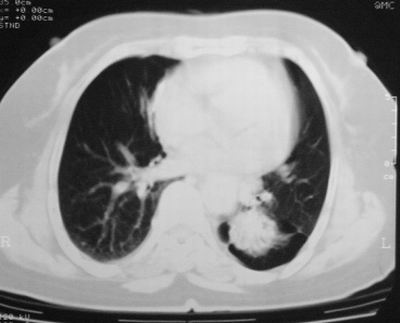

患者,女,64岁,4年前左腮腺"多形性"腺瘤手术治疗史.现复查胸部ct见左下肺块状影,该影与原左腮腺手术是否有联系?

本次复查胸部ct

左下肺软组织块影,有分叶、毛刺、空泡及胸膜牵拉征,左下肺周围性肺癌。

左肺下叶周围型肺癌,支持!(软组织肿块+分叶+毛刺+空泡+胸膜凹陷征)

左下肺软组织密度影,可见分叶,边缘可见毛刺征,胸膜增厚,强烈要求左下肺周围型肺癌

左下肺后基底段实性肿块,周围有毛刺,病变周围有肺气肿,与降主动脉间有条带状影相连,病灶4年前查体发现,纵隔内未见肿大淋巴结。考虑.肺隔离症,建议增强扫描与周围型肺癌鉴别。